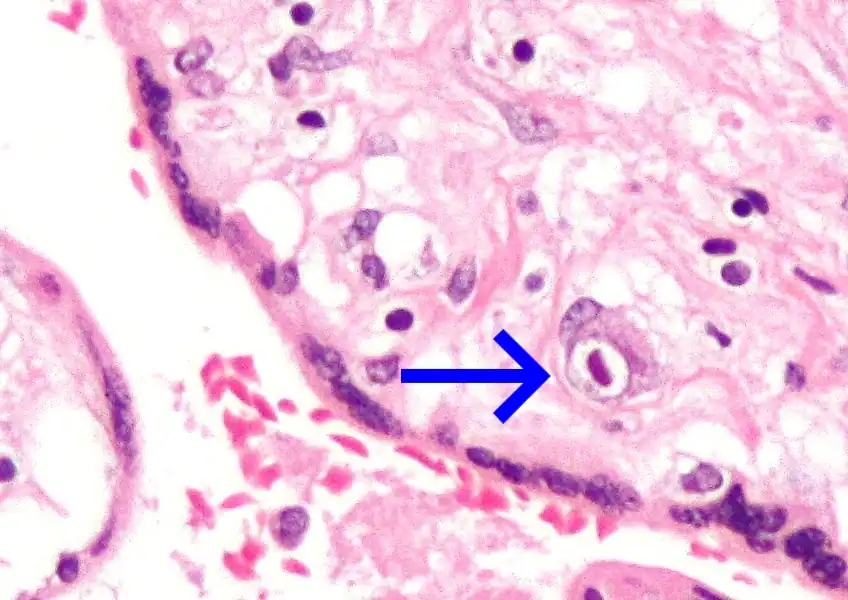

Micrografía de citomegalovirus (CMV) infección de la placenta (placentitis CMV), una infección de transmisión vertical: El característico gran núcleo de una célula infectada con CMV se ve descentrada en la parte inferior derecha de la imagen, tinción H&E. | ||

Además de infectar al feto, los patógenos transplacentarios pueden causar placentitis (inflamación de la placenta) y/o corioamnionitis (inflamación de las membranas fetales).

Placentitis por citomegalovirus (CMV)

Placentitis por citomegalovirus (CMV) -

Placentitis por citomegalovirus (CMV)

Placentitis por citomegalovirus (CMV)